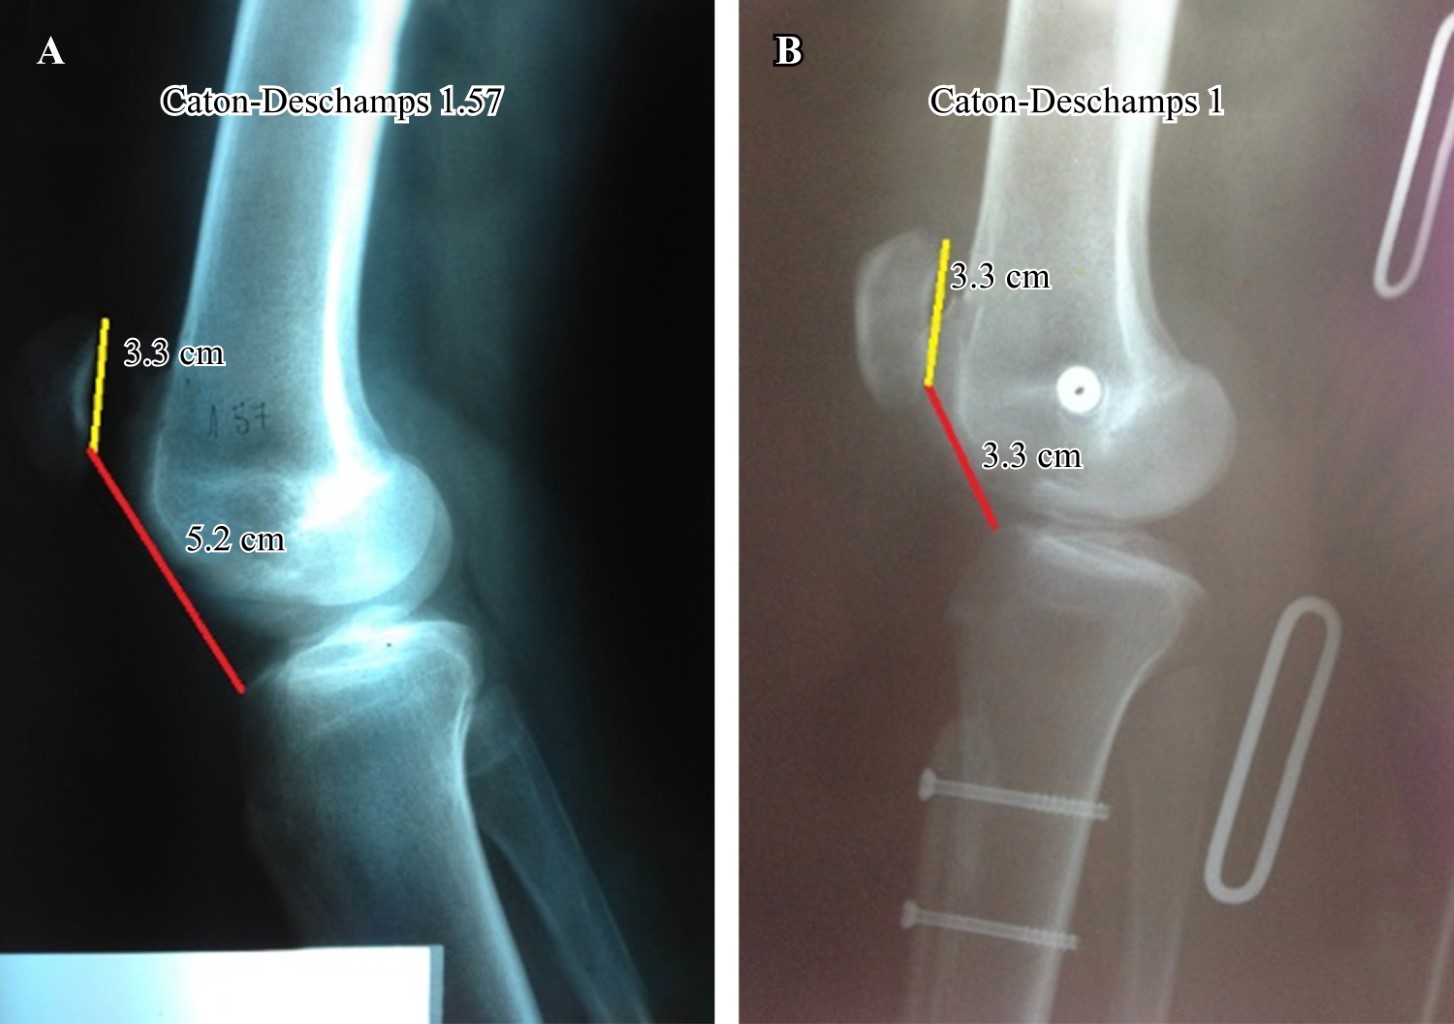

El método diagnóstico más preciso para validar una altura rotuliana excesiva es el índice de Caton-Deschamps (con la rodilla en 30o de flexión) porque se basa en una relación de puntos anatómicos fácilmente identificables y reproducibles y es posible, independientemente del tamaño de la rótula y de la configuración troclear, determinar la altura rotuliana. A su vez, fue demostrado que el método de Caton-Deschamps tiene menos variación interobservador en la comparación preoperatoria y postoperatoria y es, aparentemente, más sensible para detectar seudopatelas bajas12 (Figura 2).

El promedio del ángulo del surco troclear se modificó en los ocho casos tratados mediante la trocleoplastía. Dicho ángulo se modificó de 158o ± 19o a 140o ± 6o después de la misma (valor normal 137o ± 6o). En estos pacientes (a los cuales no se realizó osteotomía de la tuberosidad tibial anterior), el promedio de la distancia TT-TG disminuyó de 19 mm (rango 13-27 mm) a 11 mm (rango 8-17 mm) luego de la trocleplastía. Por otro lado, los pacientes que se sometieran a la transposición distal y/o medial de la tuberosidad mediante osteotomía de ésta, tuvieron una modificación en el promedio de la distancia TT-TG de 22.8 mm (rango, 20-26 mm) a 11.3 mm (rango, 6-24 mm) después del procedimiento (p ? 0.05). En este grupo el índice de Caton-Deschamps pasó de 1.26 a 0.99.